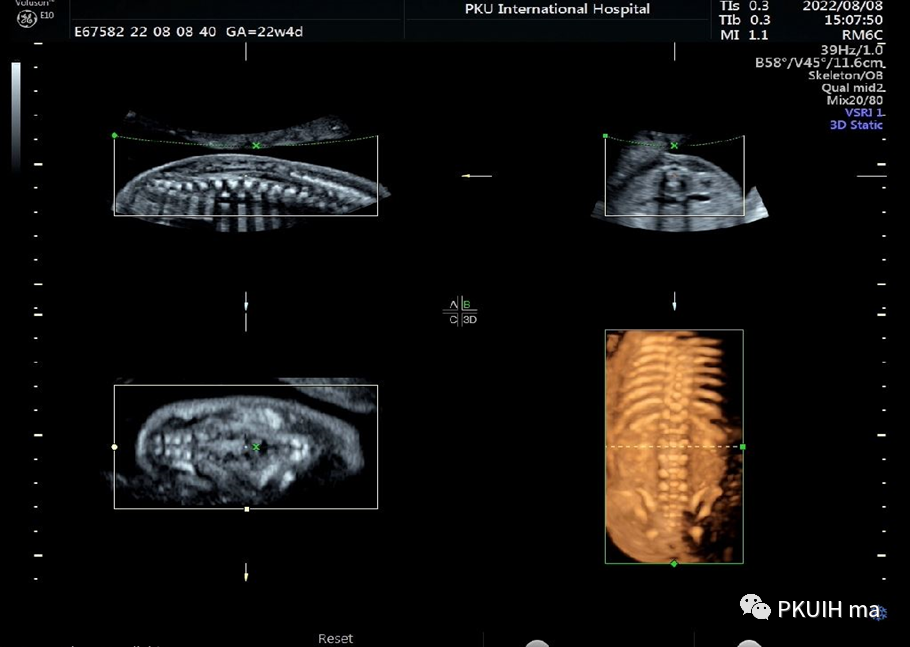

同样孕周大小胎儿做了三维图像显示热指数和机械指数分别是0.4、0.8并没有大于二维超声图像。同样下图三维超声热指数和机械指数是0.3和1.1,热指数也是很低的

骨骼模式显示整个肋骨,还可以采用水晶成像,更加直观美观